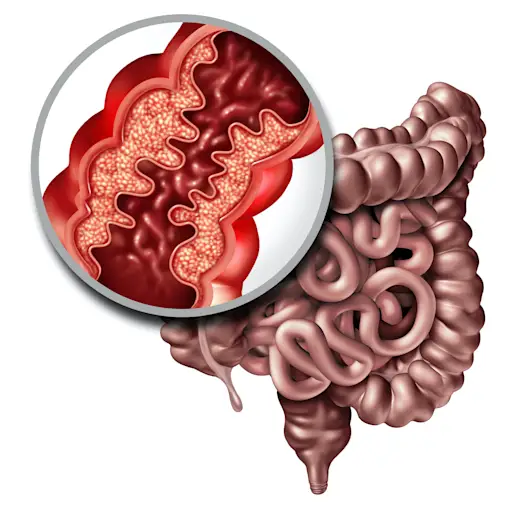

关键区别2:炎症和并发症的深度

Dalal博士说,除了炎症的位置外,UC和Crohn's的炎症深度也可能有所不同。这也可能导致并发症类型的某些差异。她说,在UC中,“炎症在肠道的衬里中往往更肤浅。”但是在克罗恩(Crohn's)中,炎症可能就是所谓的“透壁”,这实际上是“通过墙壁”的意思 - 用外行的话来说,这意味着它可以更深一点。“因此,克罗恩斯的象征会导致瘘管(连接或隧道)和脓肿(感染口袋)之类的东西,” Dalal博士解释说。